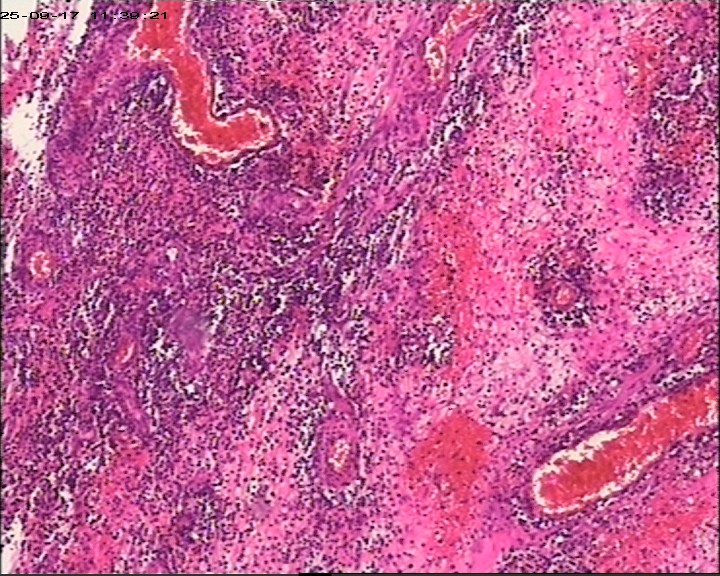

臀部组织,请帮忙看看,谢谢

性别

男

年龄

20岁

临床诊断

一般病史

藏毛窦或囊肿切开术

标本名称

臀部

大体所见

灰白灰黄碎组织一堆,大小为6.5*4*1cm。

图1

描述诊断炎性病变